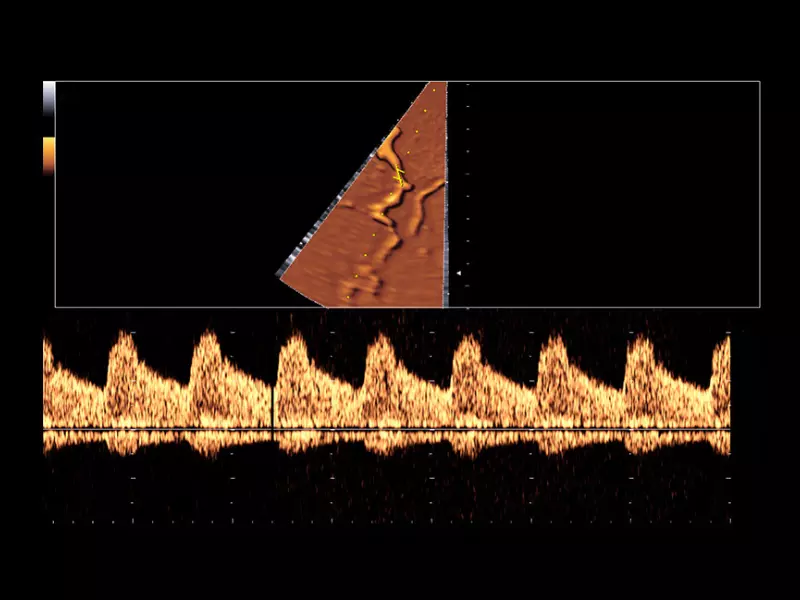

MyLab™9 Platform - PW Doppler with easyTrace optimization

MyLab™9 Platform - PW Doppler with easyTrace optimization